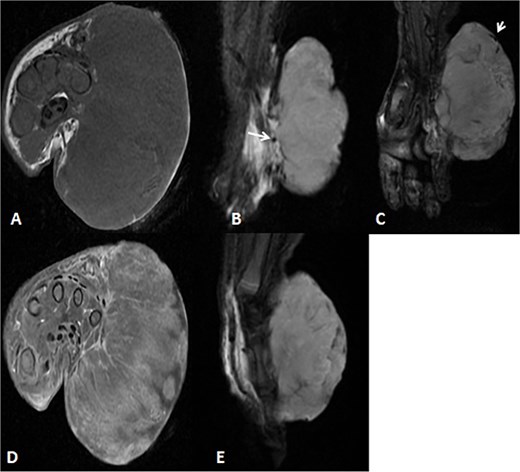

A 2-month-old girl was being followed for a suspected hemangioma on her left hand since birth. She was initially started on oral propranolol therapy but only received one dose, due to family concerns about possible side effects. The patient presented at the emergency room because of ulceration. It was observed clinically that the lesion had grown from 1.5 × 1.5 cm to 4 × 2 cm (Fig. 5). A biopsy of the lesion was taken. Ultrasound showed a partially defined large heterogeneously hyperechoic mass with internal vascularity on color Doppler with arterial and venous waveform giving atypical features of hemangioma (Fig. 6). Biopsy was done using FoundationOne Heme. The result showed stable microsatellite status and when we tested the tumor mutational burden, it showed two mutations per megabase. On MRI, a large lobulated subcutaneous soft tissue mass measuring 3.7 × 6.1 × 4.6 cm in dimensions was seen originating from the medial aspect of the left hand (Fig. 7). Internal flow voids, intermediate signal intensity on T1-weighted images, hyperintense signal on short tau inversion recovery (STIR)-weighted images, and noticeable heterogeneous enhancement on postcontrast sequences were all observed in the lesion. These imaging results raised suspicions of a malignant lesion.

MRI of left hand mass. (A) Axial T1WI shows a huge homogenous isointense mass to the corresponding hand muscles signal intensity, which is seen along the medial aspect of left hand. (B and C) Coronal STIR demonstrate heterogeneous diffuse high signal intensity of the lesion and appears inseparable with sign of invasion to the fourth and fifth digits extensor compartment/tendons as well as presence of areas of signal void (arrow). (D and E) Axial and sagittal post-contrast T1 fat-saturated images show diffuse progressive intense enhancement of the lesion.